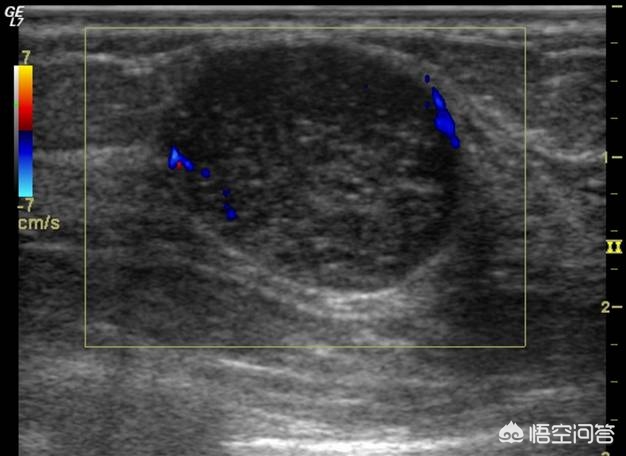

乳腺纤维腺瘤是年轻女性最常见的***结节,可以单发或者多发,活动度好,边界清楚,质地韧。乳腺纤维腺瘤在彩超下多为圆形、卵圆形均匀低回声肿物,多可见光滑清晰的包膜回声,肿块后方回声正常或轻微增强,可见侧方声影,肿块内可见伴声影的粗大钙化,肿瘤内部可显示血流或周边见少许血流信号,分布规则(蓝色)。如下图所示。